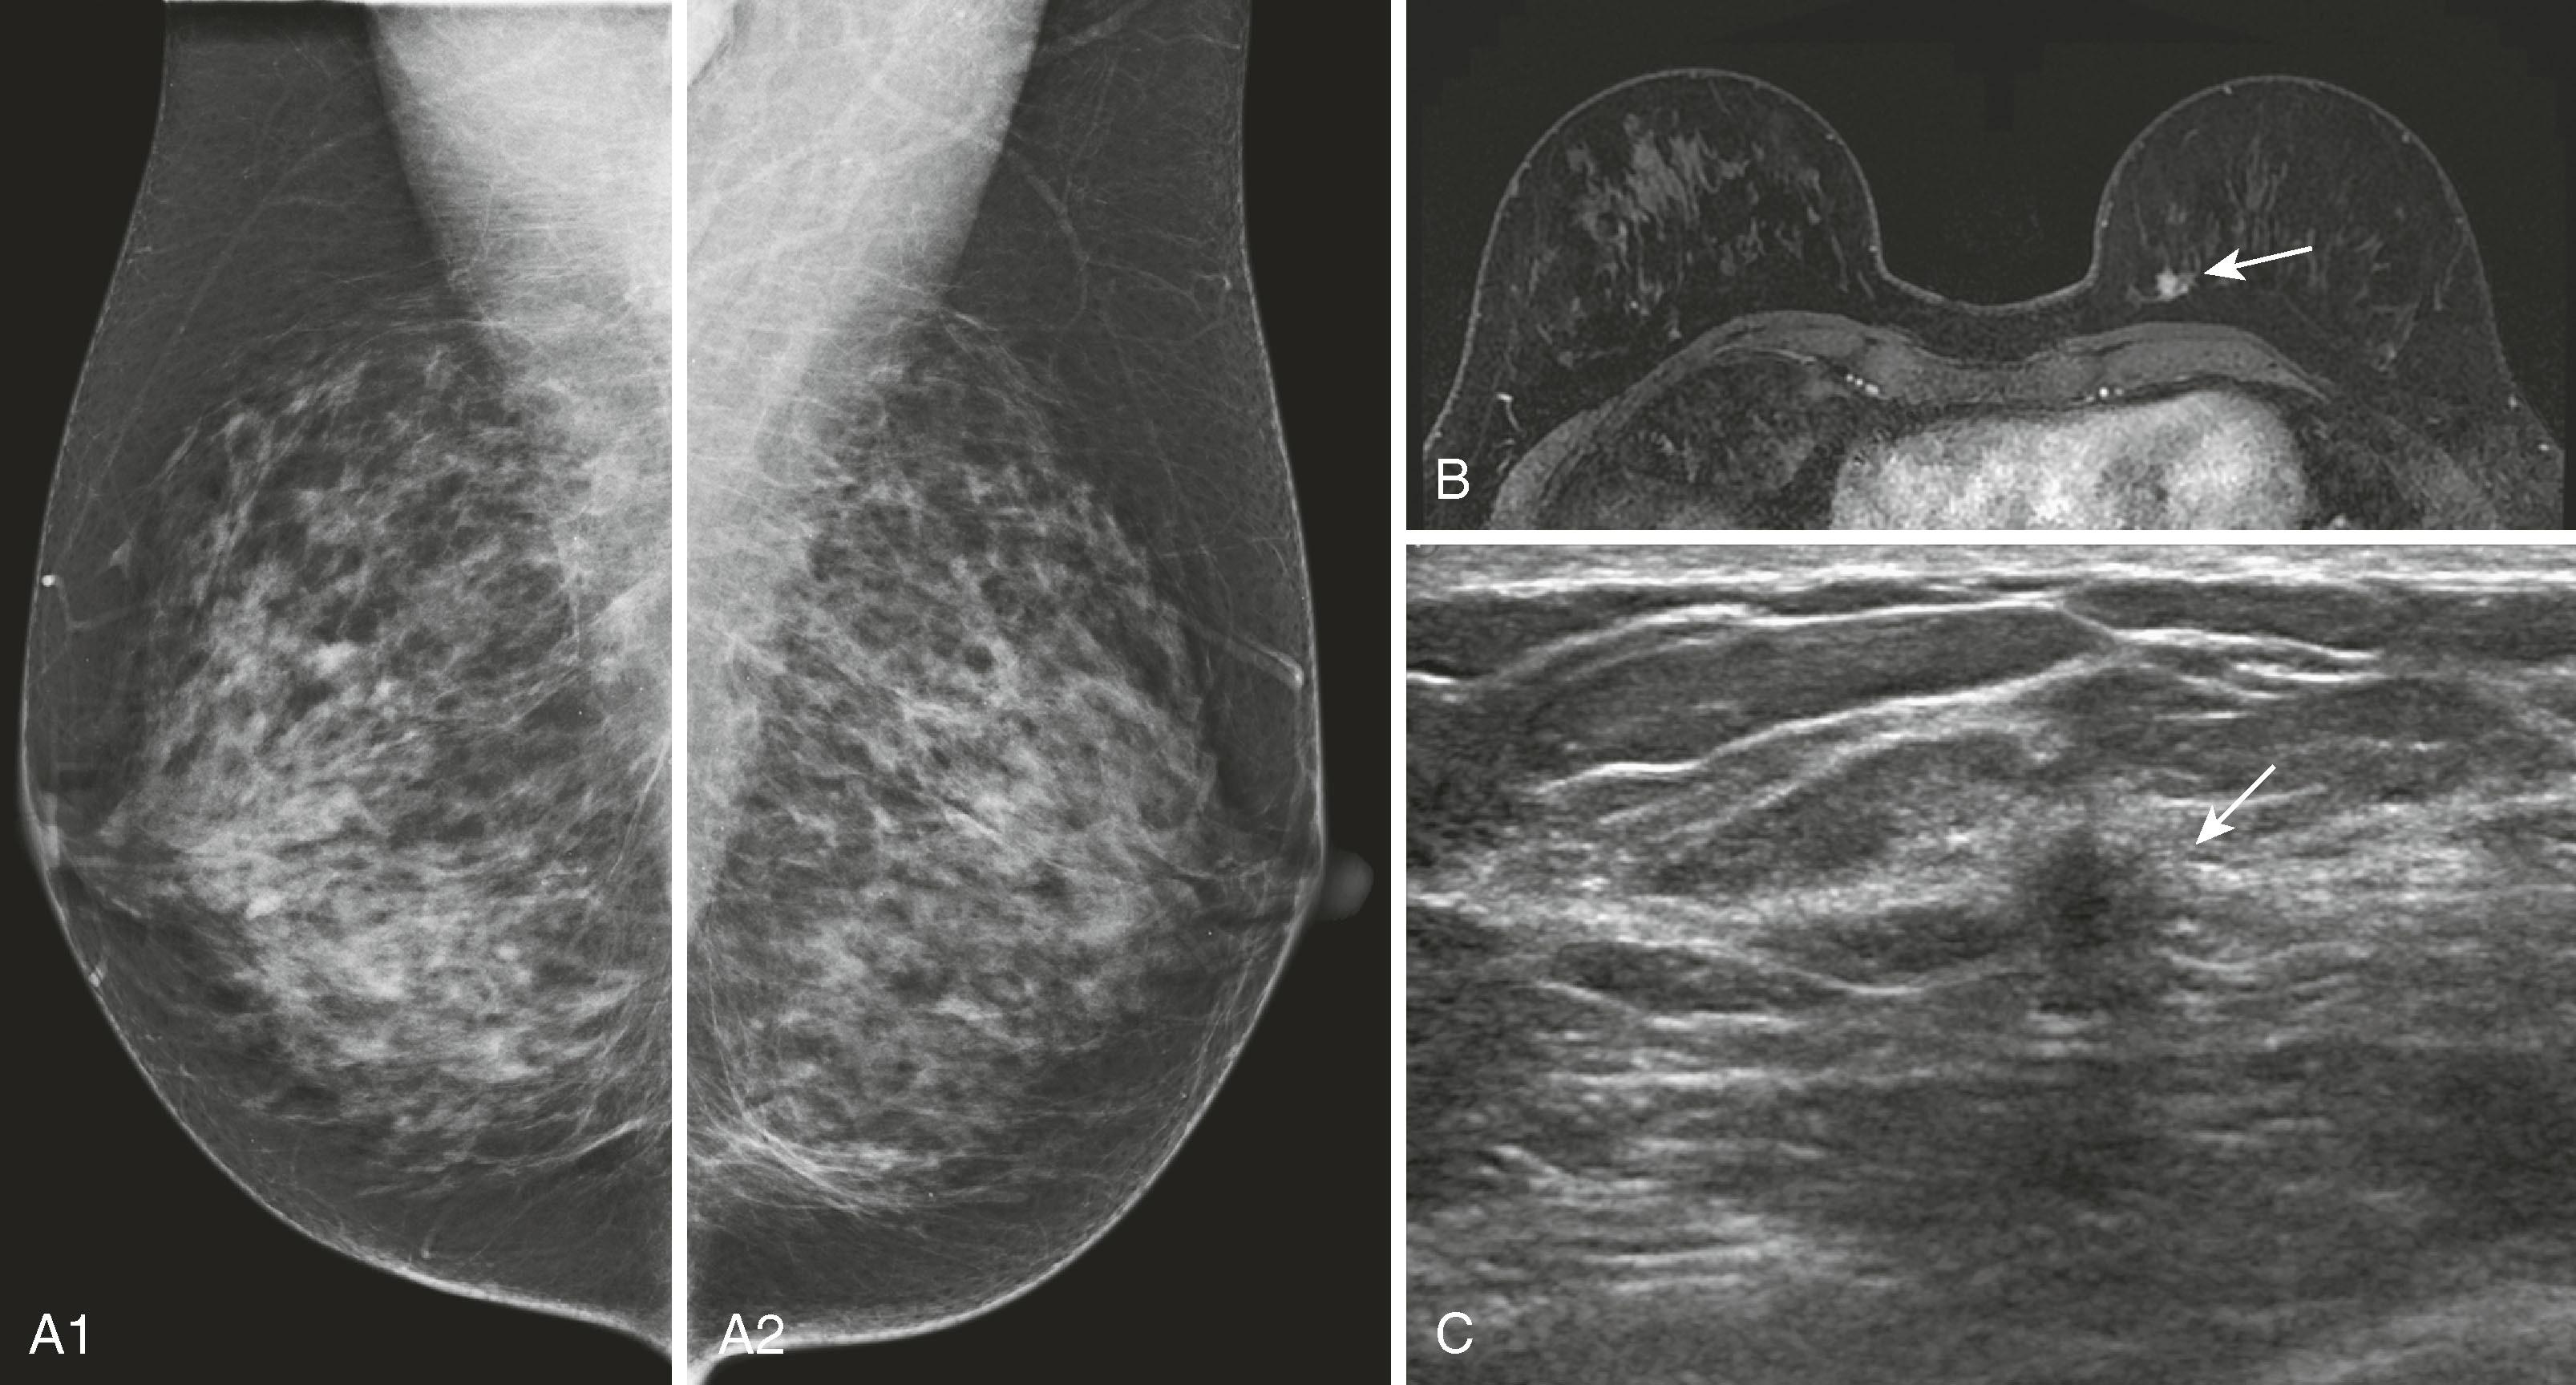

MRI for high-risk screening is now an accepted test for patients with high-risk profiles such as personal history of breast cancer and strong family history in premenopausal first-degree relative. One of the sentinel papers by Kriege and coworkers found that of 1,909 high-risk women screened with clinical breast examination, mammography, and MRI, the sensitivities were 17.9%, 33.3%, and 79.5%, respectively. The conclusion was that “MRI appears to be more sensitive than mammography in detecting tumors in women with an inherited susceptibility to breast cancer.” Initially published guidelines by the American Cancer Society helped to identify patients for whom screening breast MRI would be most effective. The published guidelines stated that women who have a greater than 20% lifetime risk for the development of breast cancer should undergo yearly MRI and mammography. The topic of breast cancer screening, especially for women at high risk, has been elaborated on by others, notably Monticciolo and colleagues, with recommendations from the Society of Breast Imaging and the American College of Radiology regarding the use of mammography, breast MRI, breast ultrasound, and other technologies. Figs. 8.33 and 8.34 demonstrate two screening patients with strong family histories of breast cancer; one is a false positive and the other a true positive.

Fig. 8.33, ( A ) High-risk patient presents for screening magnetic resonance imaging (MRI), which shows several small enhancing foci (arrow) in the midleft breast. ( B ) Patient underwent MRI-guided biopsy, and pathology was benign, revealing fibrocystic changes (arrow) . This is considered a false positive.

Fig. 8.34, ( A1 and A2 ) Bilateral screening mammography findings are negative. ( B ) Magnetic resonance imaging demonstrates a small enhancing lesion (arrow) in the medial left breast. ( C ) Patient returned for second-look ultrasound, which revealed a hypoechoic lesion with irregular margins (arrow) . Ultrasound-directed biopsy was performed.